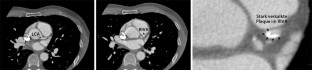

Abb. 3